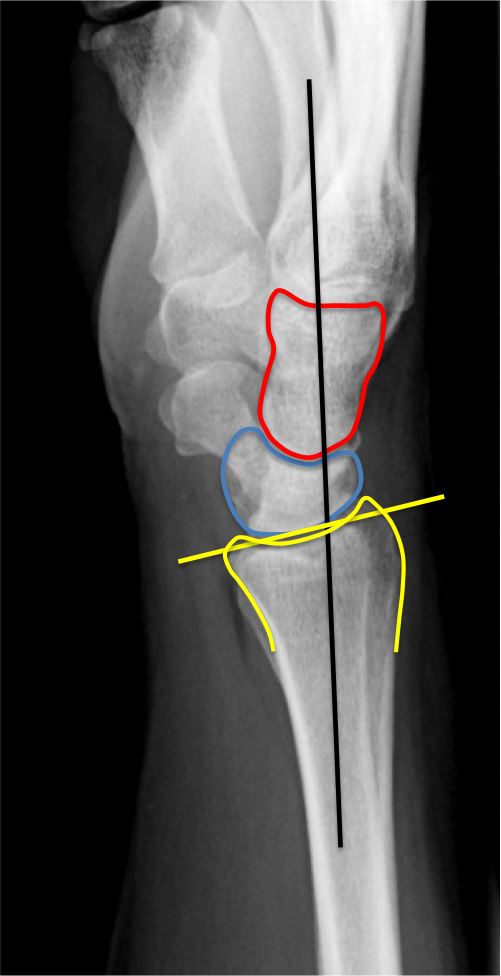

Em Rems Category Archive Wrist Xr

Hand And Wrist Radiology Key

The Wrist

Wrist Fractures Pdf